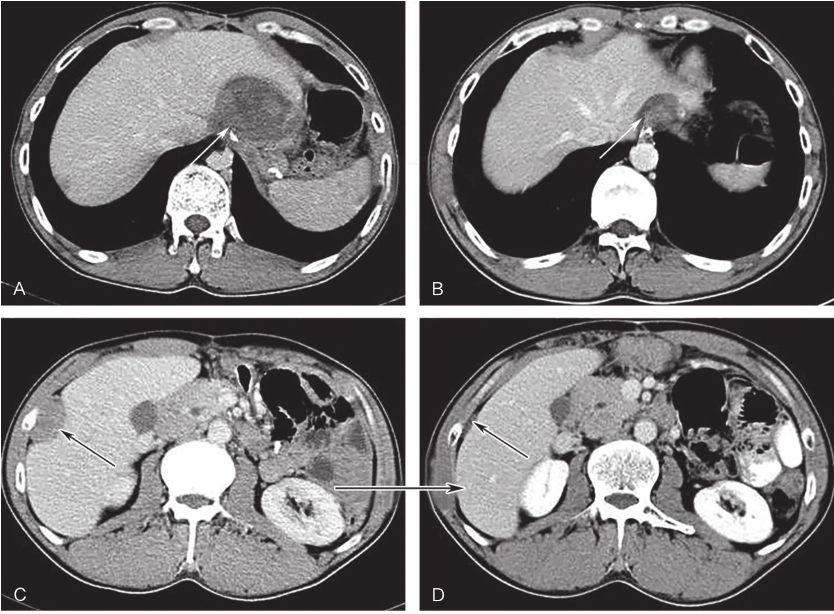

全腹部增强CT:左上腹软组织肿块,大小约16.4cm×12.3cm,考虑胃底大弯侧来源GIST伴左侧膈肌侵犯可能性大,需与淋巴瘤、神经鞘瘤、平滑肌瘤等其他胃黏膜下少见肿瘤鉴别(图1、图2)。

图1首诊全腹增强CT示胃底大弯侧来源GIST

于2012年10月13日开始口服伊马替尼400mg/d 治疗。治疗3个月后CT评估肿瘤大小为120mm×87mm,治疗6个月后CT评估肿瘤大小为92mm×65mm。治疗8个月后CT示:胃底大弯侧GIST,伊马替尼治疗后,肿瘤明显退缩,大小为89mm×63mm,病灶与左侧膈肌接触面缩小,分界较前清晰(图3)。此间规律口服伊马替尼,主要不良反应为1~2度食欲减退、乏力、手足综合征,未予特殊处理,自行缓解。

2016年1月4日,开始口服舒尼替尼37.5mg/d,连续用药。此间出现高血压、手足综合征、乏力等1~2度不良反应,未予特殊处理,自行缓解。每3个月复查全腹CT。口服舒尼替尼3个月、6个月、9个月后吻合口病灶大小分别为:51mm×49mm、35mm×26mm、31mm×15mm,肝被膜下病灶分别为:36mm×20mm、21mm×6mm、21mm×5mm,最佳疗效PR(图5)。

图3术前治疗8个月后全腹增强CT

图4伊马替尼辅助治疗30个月后全腹增强CT(冠状位)

白色箭头示吻合复发病灶,黑色箭头示肝包膜转移灶

图5舒尼替尼治疗9个月后增强CT表现

A、C.治疗前病灶;B、D.治疗9个月后病灶;白色箭头示吻合复发病灶,黑色箭头示肝包膜转移灶